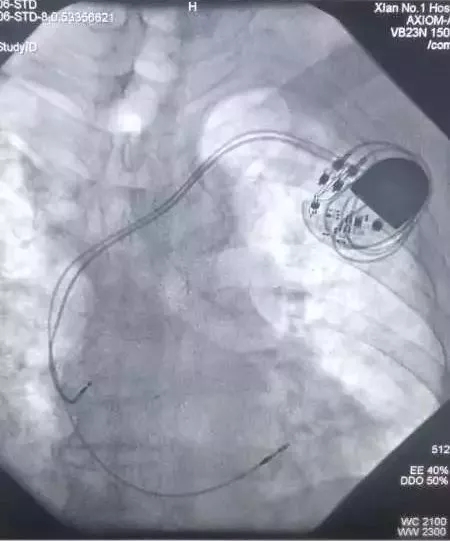

CCU成功实施成人导航首例双主动电极抗核磁起搏器植入术